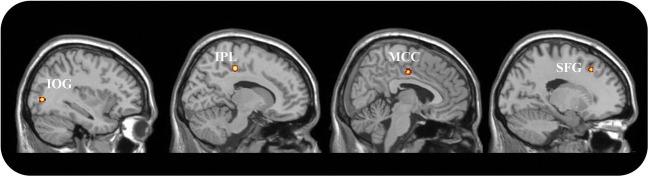

Pedophilia is a disorder of public concern because of its association with child sexual offense and recidivism. Previous neuroimaging studies of potential brain abnormalities underlying pedophilic behavior, either in idiopathic or acquired (i.e., emerging following brain damages) pedophilia, led to inconsistent results. This study sought to explore the neural underpinnings of pedophilic behavior and to determine the extent to which brain alterations may be related to distinct psychopathological features in pedophilia. To this aim, we run a coordinate based meta-analysis on previously published papers reporting whole brain analysis and a lesion network analysis, using brain lesions as seeds in a resting state connectivity analysis. The behavioral profiling approach was applied to link identified regions with the corresponding psychological processes. While no consistent neuroanatomical alterations were identified in idiopathic pedophilia, the current results support that all the lesions causing acquired pedophilia are localized within a shared resting state network that included posterior midlines structures, right inferior temporal gyrus and bilateral orbitofrontal cortex. These regions are associated with action inhibition and social cognition, abilities that are consistently and severely impaired in acquired pedophiles. This study suggests that idiopathic and acquired pedophilia may be two distinct disorders, in line with their distinctive clinical features, including age of onset, reversibility and modus operandi. Understanding the neurobiological underpinnings of pedophilic behavior may contribute to a more comprehensive characterization of these individuals on a clinical ground, a pivotal step forward for the development of more efficient therapeutic rehabilitation strategies.

恋童癖是一个公众关注的问题,因为它与儿童性犯罪和累犯有关。以前对潜在的恋童癖行为的神经影像学研究,无论是特发性的还是获得性的(即脑损伤后出现的),都得出了不一致的结果。这项研究旨在探索恋童癖行为的神经基础,并确定大脑改变与恋童癖的不同心理病理特征之间的关系程度。为此,我们对以前发表的报告全脑分析和病变网络分析的论文进行了基于坐标的荟萃分析,使用病变作为静息状态连接分析的种子。行为分析方法被用来将确定的区域与相应的心理过程联系起来。虽然在特发性恋童癖中没有发现一致的神经解剖学改变,但目前的结果支持所有导致获得性恋童癖的病变都位于一个共享的静息状态网络内,该网络包括后中线结构、右侧下颞叶和双侧眶额皮层。这些区域与动作抑制和社会认知有关,而获得性恋童癖者的这些能力一直受到严重损害。这项研究表明,特发性和获得性恋童癖可能是两种不同的障碍,与它们独特的临床特征一致,包括发病年龄、可逆性和作用方式。了解恋童癖行为的神经生物学基础可能有助于更全面地描述这些个体的临床特征,这是开发更有效的治疗康复策略的关键一步。